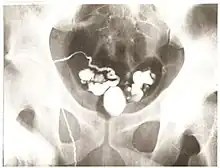

Vasography with a prostatic cyst and seminal vesicles filled with iodinated contrast

Vasography is an X-ray study of the vas deferens to see if there is blockage, oftentimes in the context of male infertility.[1] An incision is made in the scrotum, contrast is injected in the vas deferens, and X-rays are taken from different angles.[1] Thus, it is an invasive procedure and carries risk of iatrogenic scarring and obstruction of the vas.[2] Vasography has traditionally been considered the gold standard imaging modality for evaluating the seminal tract patency.[3]